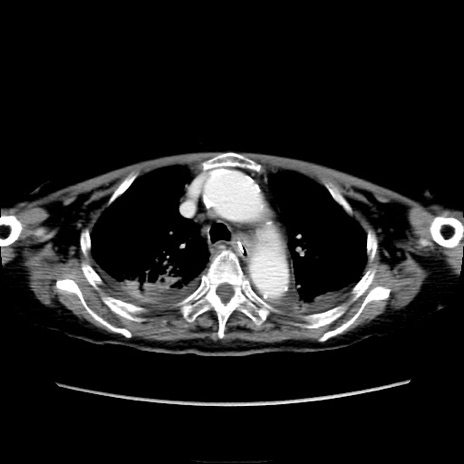

他院CT

横断像